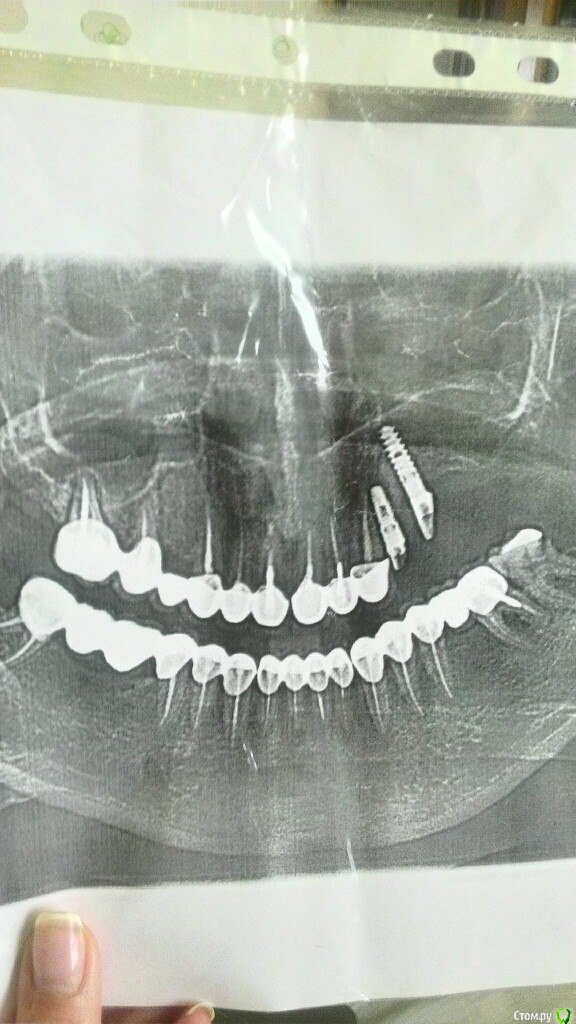

Надежда В. Опубликовано 29 августа, 2017 Поделиться Опубликовано 29 августа, 2017 (изменено) Уважаемые специалисты! Нужны ваши мнения по поводу целесообразности удаления прижившегося импланта. Он был поставлен около 2 лет назад в верхнюю челюсть. Ничего не беспокоило, а 2 недели назад начался левоосторонний гайморит. Как выяснилось, имплант торчит в гайморовой пазухе. На данный момент гайморит практически пролечен. Лор говорит, что надо проконсультироваться со стоматологами по поводу удаления импланта. Стоматологи говорят, что решение об удалении я должна принять сама. Изменено 29 августа, 2017 пользователем Надежда В. Ссылка на комментарий

Bier Опубликовано 29 августа, 2017 Поделиться Опубликовано 29 августа, 2017 у вас с другой стороны зуб - очаг инфекции. А гайморит бывает и не связанный с зубами. Более того для понимания расположения имплантата нужно посмотреть КТ, а не панорамный снимок. Ссылка на комментарий

Надежда В. Опубликовано 29 августа, 2017 Автор Поделиться Опубликовано 29 августа, 2017 С другой стороны киста уже давно. КТ добавила. у вас с другой стороны зуб - очаг инфекции. А гайморит бывает и не связанный с зубами. Более того для понимания расположения имплантата нужно посмотреть КТ, а не панорамный снимок. Ссылка на комментарий